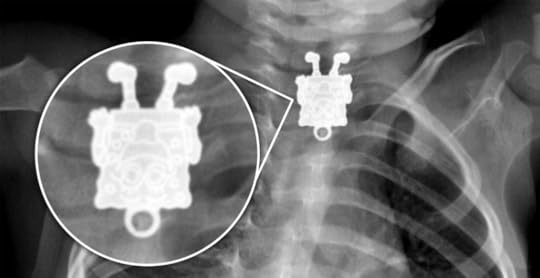

Image courtesy of Dr Ghofran Ageely, Radiopaedia.org. From the case rID: 33663

Some of the more jaw-dropping things people have swallowed would shock even the most seasoned physician, including lighters, a full-sized toothbrush, and a cellphone, some of which were in the patient’s body for upward of a decade!

For smaller items, doctors can use endoscopes to retrieve the foreign object, but in these instances, they are often forced to operate.